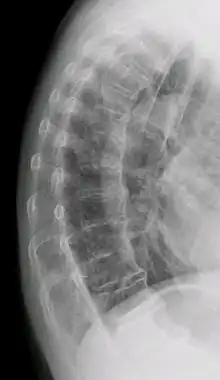

| DISH in an 80 year old female, also with T11 fracture. | |